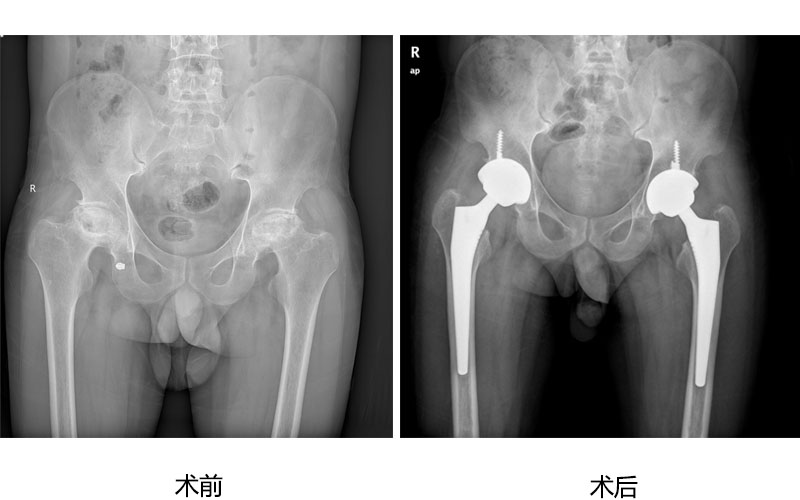

人工关节置换为广大高龄老年股骨颈骨折、股骨粗隆间骨折病人提供快速康复治疗,为严重股骨头坏死、膝关节炎病人解除病痛,恢复正常行走功能。 病例展示如下:

股骨头坏死微创全髋人工关节置换术